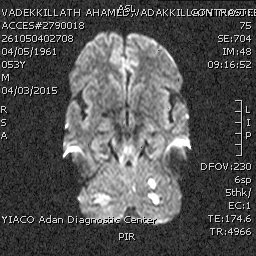

• Multiple variable sized foci of altered MR signals in both cerebellar hemispheres with the largest one diameter 22 x 12 mm on the right side.

• Another focus in the left thalamus and in the left occipital region.

• Small vessel ischemic disease with grade I Fazekas classification.

• Non visualization of the left vertebral artery (occluded) on MR angiography.

• On the light of the MR findings; picture is suggestive of posterior circulation insufficiency with multiple infarcts as described with completely occluded left vertebral artery.